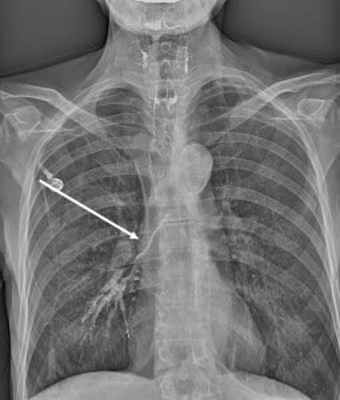

2) СКТ органов грудной полости: КТ-признаки ушиба лёгких. Перелом левой лопатки, левой плечевой кости, правого акромиона.

К 9 суткам, сознание - 5 баллов, взгляд не фиксирует, не следит, расходящееся косоглазие. Спустя 2 недели после полученных травм на компьютерной томографии органов грудной клетки выявлены признаки правосторонней гиповентиляционной пневмонии.

Лучевое исследование включает выполнение рентгеноскопии и рентгенографии легких, эзофагографии, МСКТ грудной клетки. Контрастное исследование пищевода проводят очень осторожно, используя водорастворимые или масляные вещества, которые вводятся через зонд (применение сульфата бария в этих случаях недопустимо). Трахеопищеводный свищ требует проведения тщательной дифференциальной диагностики с изолированной атрезией и стенозом пищевода, гастроэзофагеальным рефлюксом, ахалазией кардии, дисфагией различного генеза.

- Обязательным является проведение рентгенографии и рентгеноскопии пищевода с водорастворимым контрастным веществом (барий использовать не рекомендуется, рисунок 1, 2).

Рисунок 1. Пищеводно-респираторный свищ при рентгенографии/рентгеноскопии пищевода